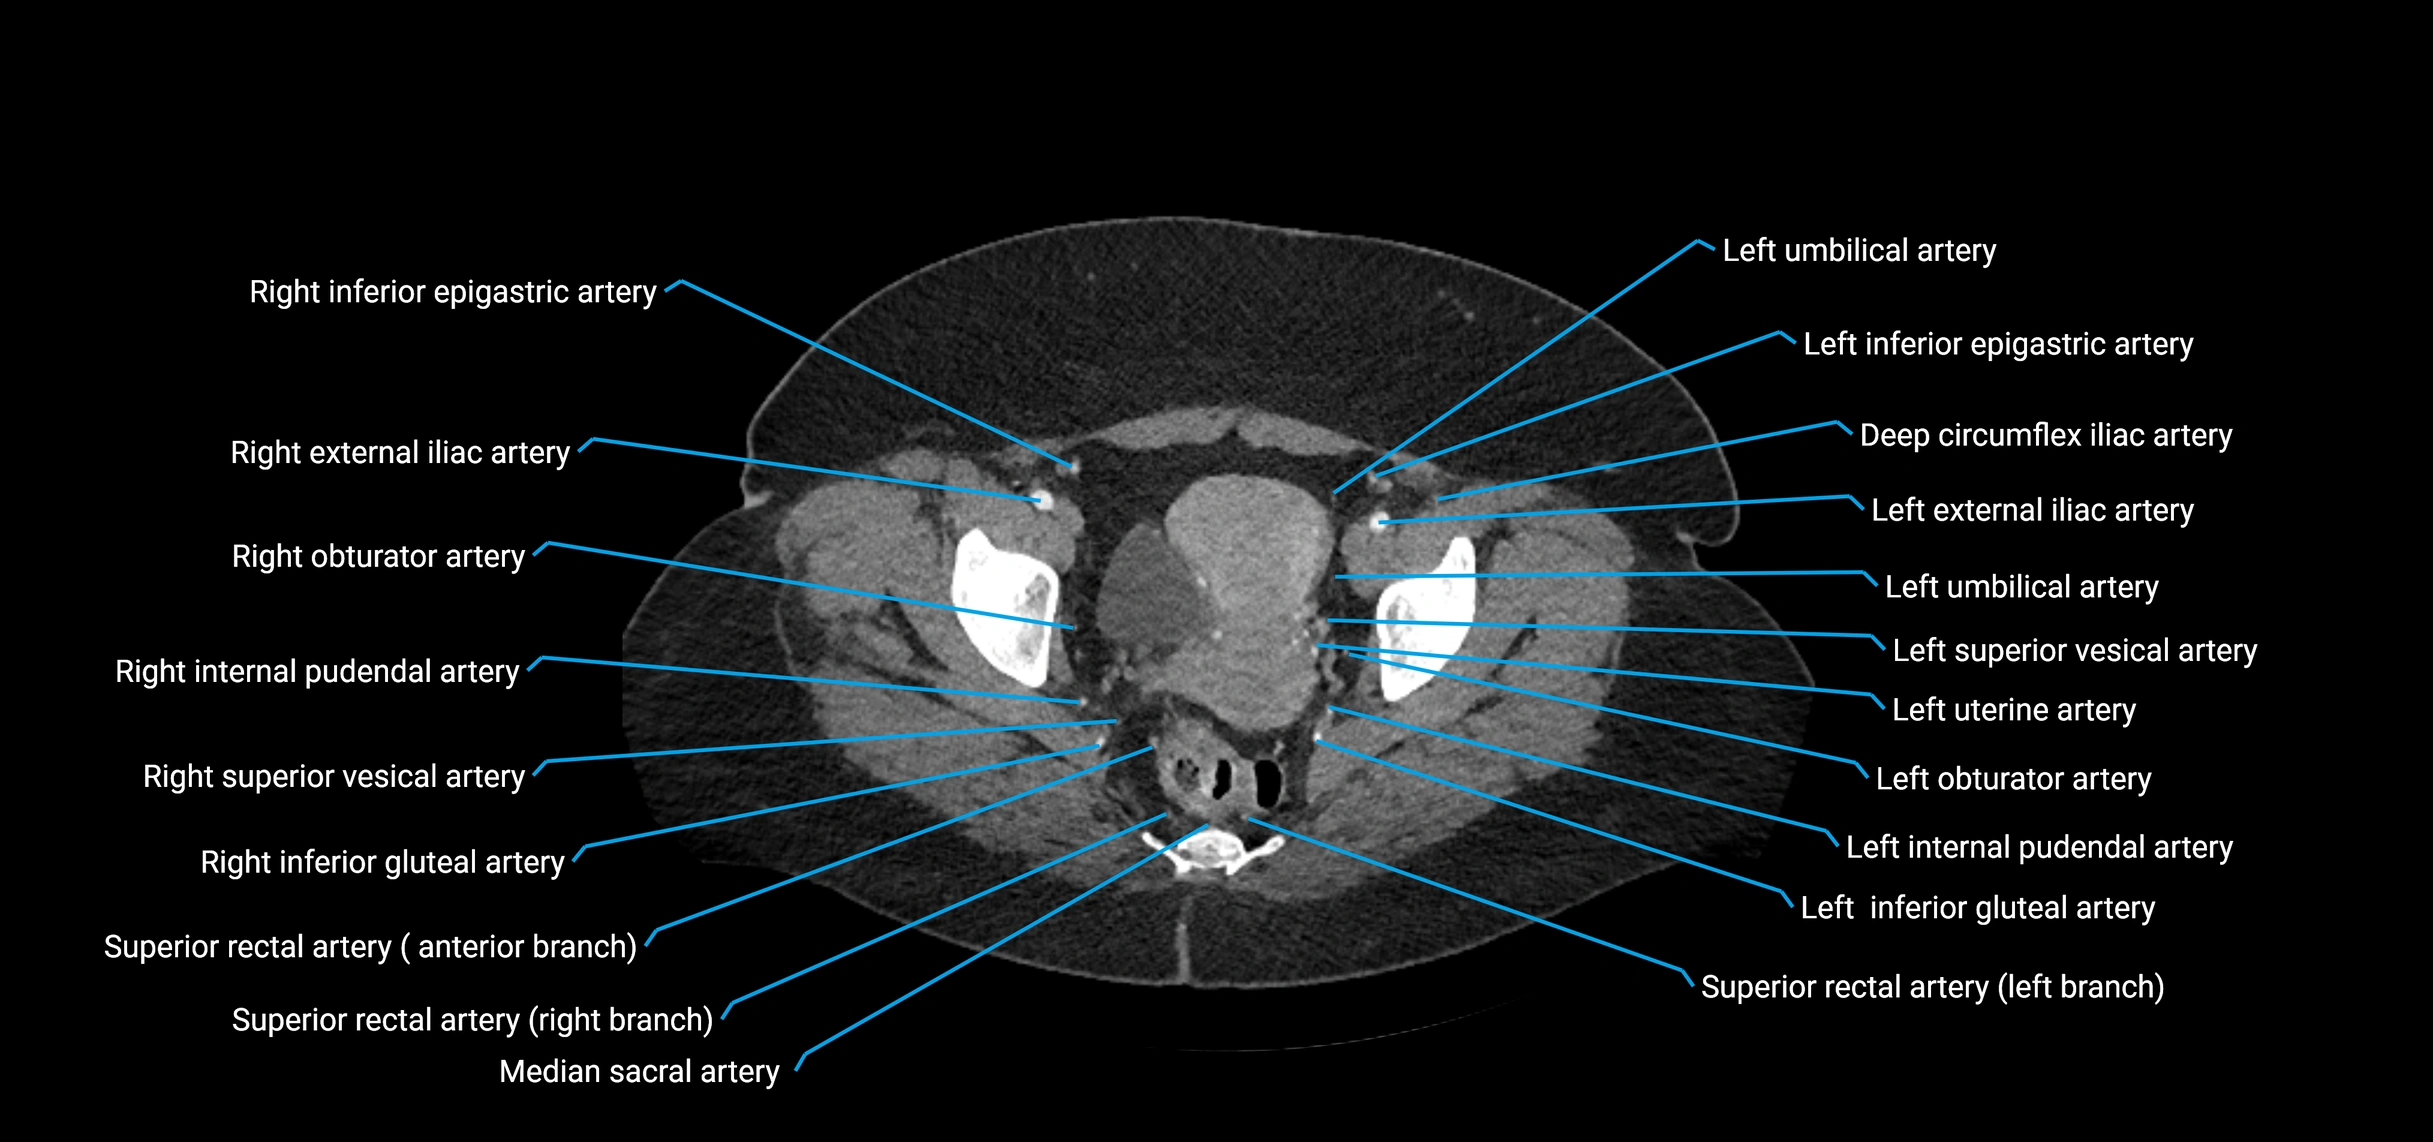

Contrast-enhanced CT (CTA):

• Gold standard for abdominal aortic imaging

• Provides excellent detail of lumen, wall, aneurysm, thrombus, and branch vessels

• Multiplanar and 3D reconstructions help in aneurysm measurement, stent graft planning, and dissection evaluation

• Detects acute rupture, traumatic injury, or occlusion with high sensitivity